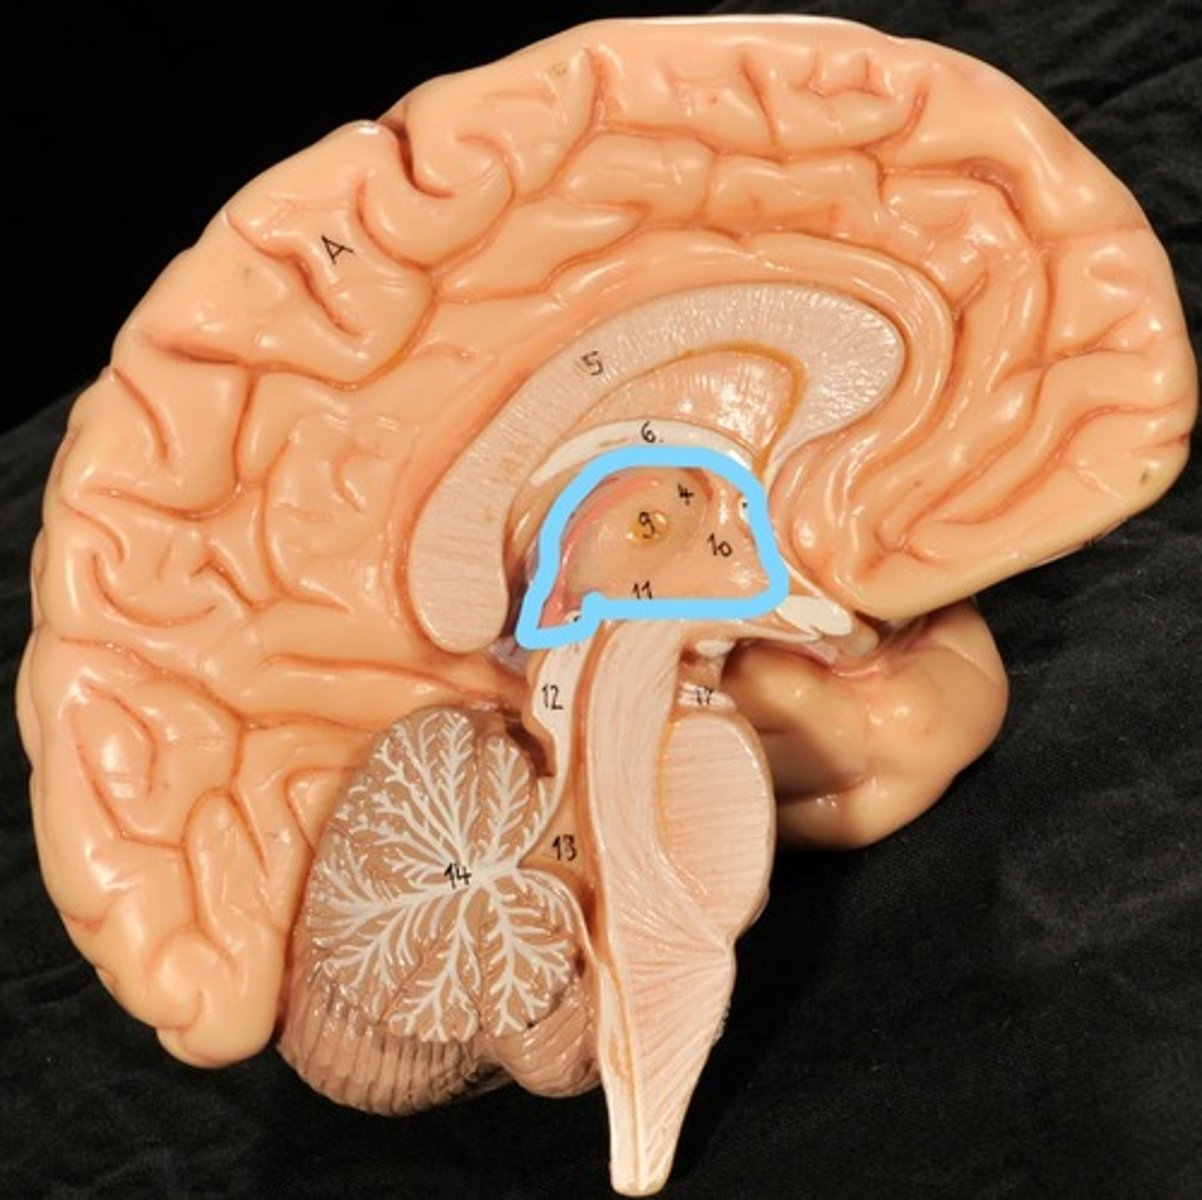

Identify structures of midsagittal brain

Corpus callosum

Diencephalon

thalamus, third ventricle, hypothalamus, epithalamus

Thalamus

Third Ventricle

Hypothalamus

Epithalamus (pink line)

Brain stem

Pons

Medulla oblongata

choroid plexus of third ventricle

produces cerebrospinal fluid

Third ventricle

cerebral aqueduct (midbrain)

midbrain

Fourth ventricle

Central Canal of brain

Takes Cerebrospinal fluid down to the spinal cord

Thalamus